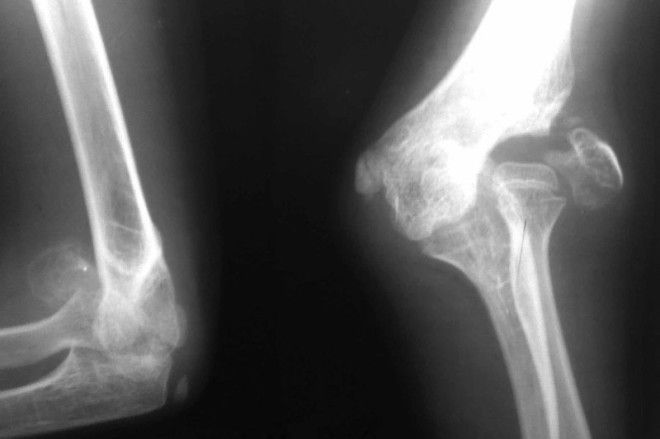

5. Самое распространенное заболевание, поражающее человеческий скелет — остеопороз. Этот недуг характеризуется снижением костной массы и повышенной ломкостью костей. По данным ВОЗ, в Европе смертность от переломов, связанных с остеопорозом, превышает количество смертей от онкологических заболеваний.